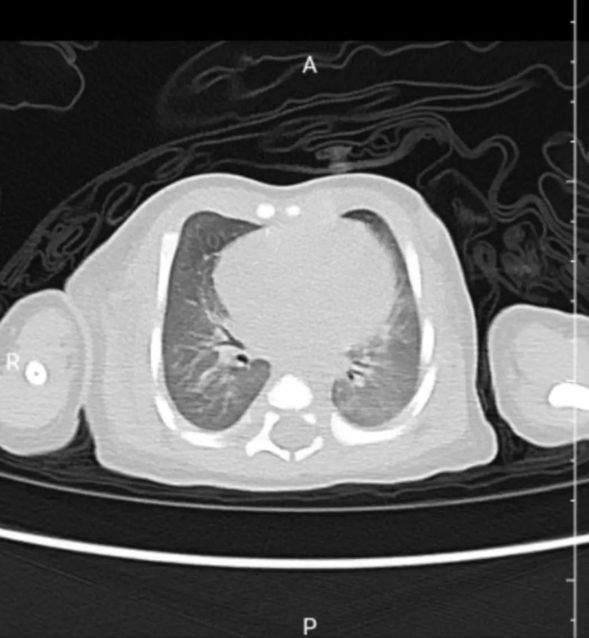

出院前复查胸部CT影像

在杜龙主任的带领下,全体医护的共同努力下,小宝宝成功完成了高频呼吸机辅助通气,复查血气分析和胸部CT显示病情逐渐得到控制,小患儿不再烦躁不安、呼吸困难的情况得到缓解,人机配合良好,患儿熟睡的样子看起来很是舒服。在4天的日日夜夜的守护下,小宝宝辅助通气的呼吸机由高频转为常频,后顺利脱机。经过后续的治疗,小宝宝顺利出院。